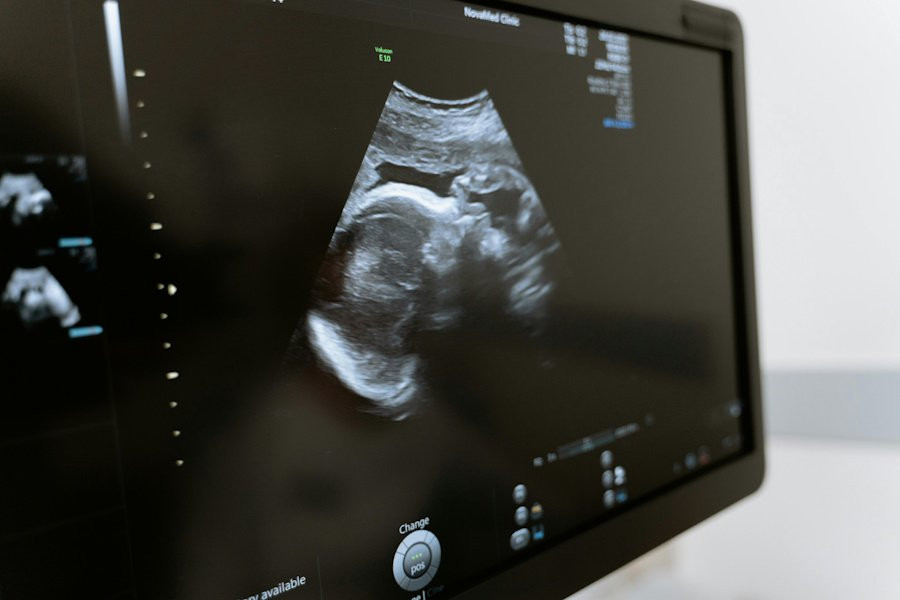

Ученые из McGill University (Канада) провели масштабное исследование, которое показало, что суррогатные матери сталкиваются со значительно более высоким риском серьезных осложнений во время беременности. Результаты работы были опубликованы в медицинском журнале Annals of Internal Medicine.

Эксперты изучили данные о 863 017 одноплодных родах, из которых 806 приходилось на гестационных носителей — так называют женщин, вынашивающих детей для других людей. Результаты исследования оказались тревожными: вероятность тяжелых материнских заболеваний среди суррогатных матерей составила 7,8%. Это более чем в три раза выше, чем у женщин, зачавших ребенка самостоятельно, и почти в два раза выше по сравнению с женщинами, прошедшими процедуру экстракорпорального оплодотворения (ЭКО).